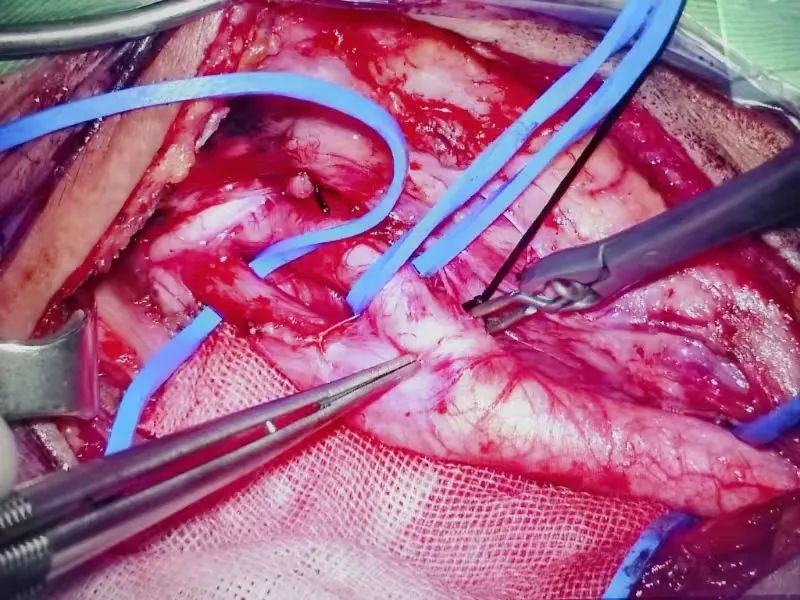

颈内动脉剥脱患者的经历,便是个性化治疗的有力见证。这位患者辗转多家医院,被诊断为颈内动脉狭窄,来到淮南东方总院。神经外科医疗中心张德辉院长团队深知手术风险与难度,先为其进行脑血管造影,精准掌握血管病变情况。随后,在全麻下为患者施行颈内动脉剥脱术。手术过程中,医生凭借高超技艺,小心翼翼地操作,避开周围复杂的神经和血管,将颈内动脉斑块完全剥离,术后颈内动脉血流再通良好。

另一位烟雾病患者,5个月前因脑出血查出双侧烟雾病,在外院治疗。3个月前,为进一步治疗烟雾病,遂来我院,由于出血在右侧,医疗中心吴鹏副院长率领团队为其先行右侧烟雾病搭桥手术。手术精细复杂,需要将头皮动脉血管与脑表面血管精准缝合,恢复脑部血供。术后患者恢复满意,此次再次来行左侧烟雾病搭桥手术。每一步治疗,都根据患者病情变化与身体恢复情况精心规划。